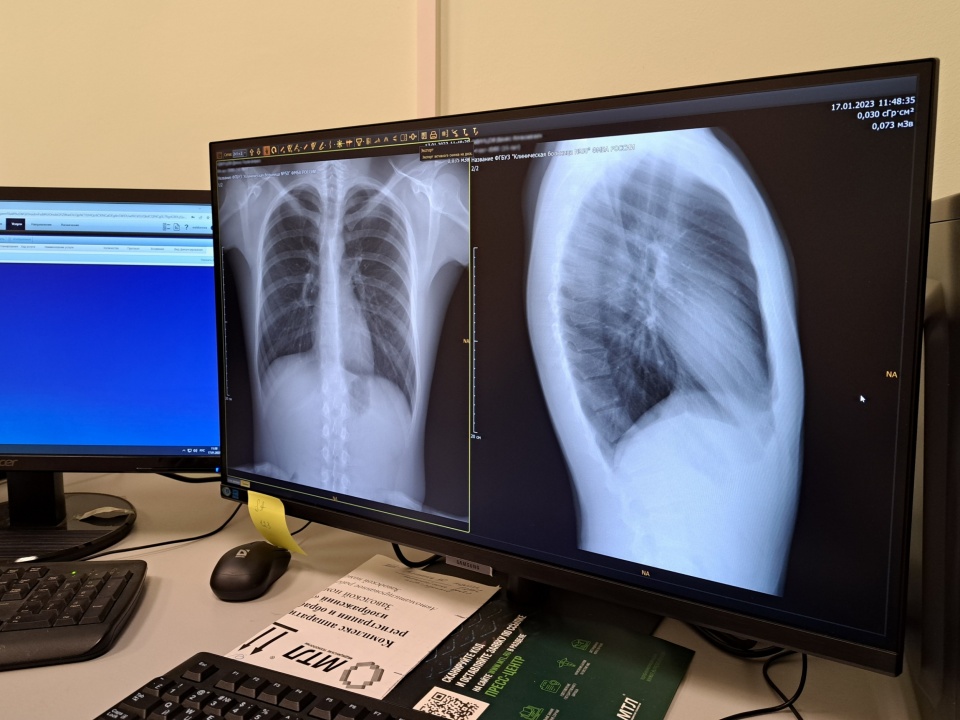

Снимок легких пациента после прохождения флюорографии на новом оборудовании: